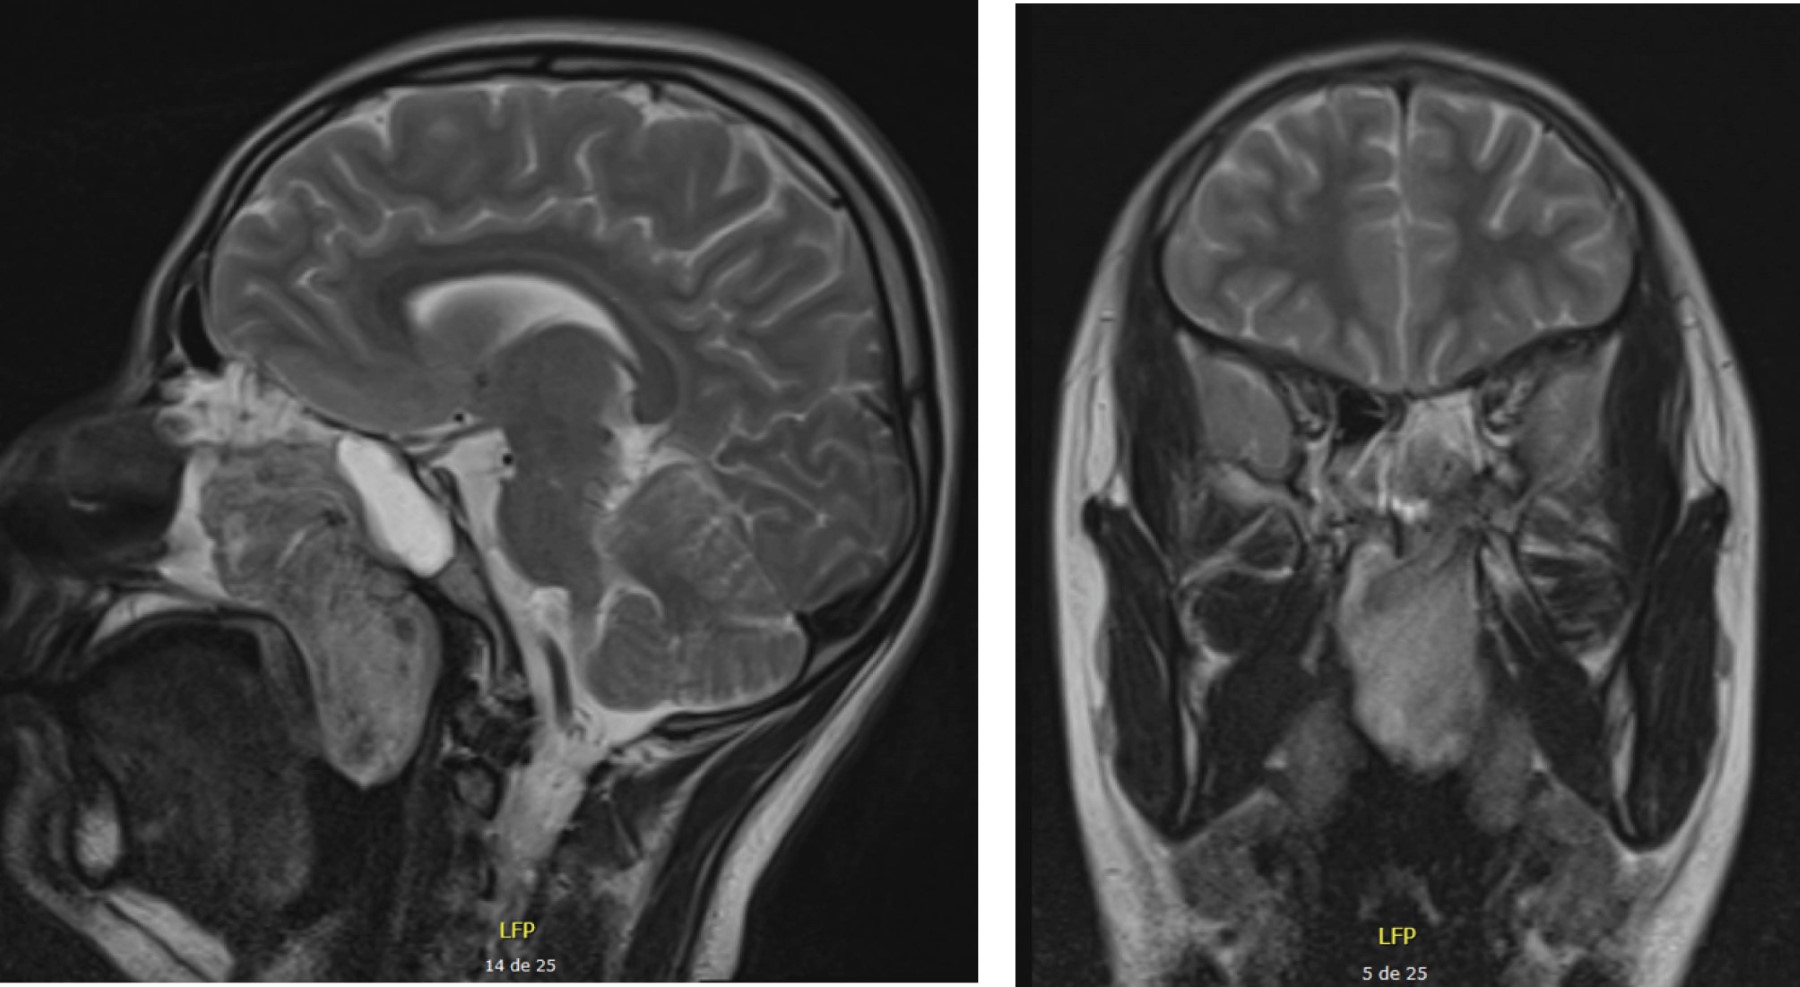

En RM se identifica lesión a nivel de la fosa pterigopalatina izquierda con extensión antrocoanal, es de aspecto sólido, muestra realce ávido y homogéneo tras la administración del medio de contraste, tiene dimensiones aproximadas de 6.3 × 2.8 × 2.8 cm en sus ejes mayores. La lesión encasilla a los cornetes superior, medio e inferior izquierdo, erosiona la pared anterior del seno esfenoidal izquierdo en donde se evidencia un pequeño componente tumoral, así como extensión a la nasofaringe; se observa aporte arterial de la arteria maxilar izquierdo hacia anterior (Figura 4).

Figura 4